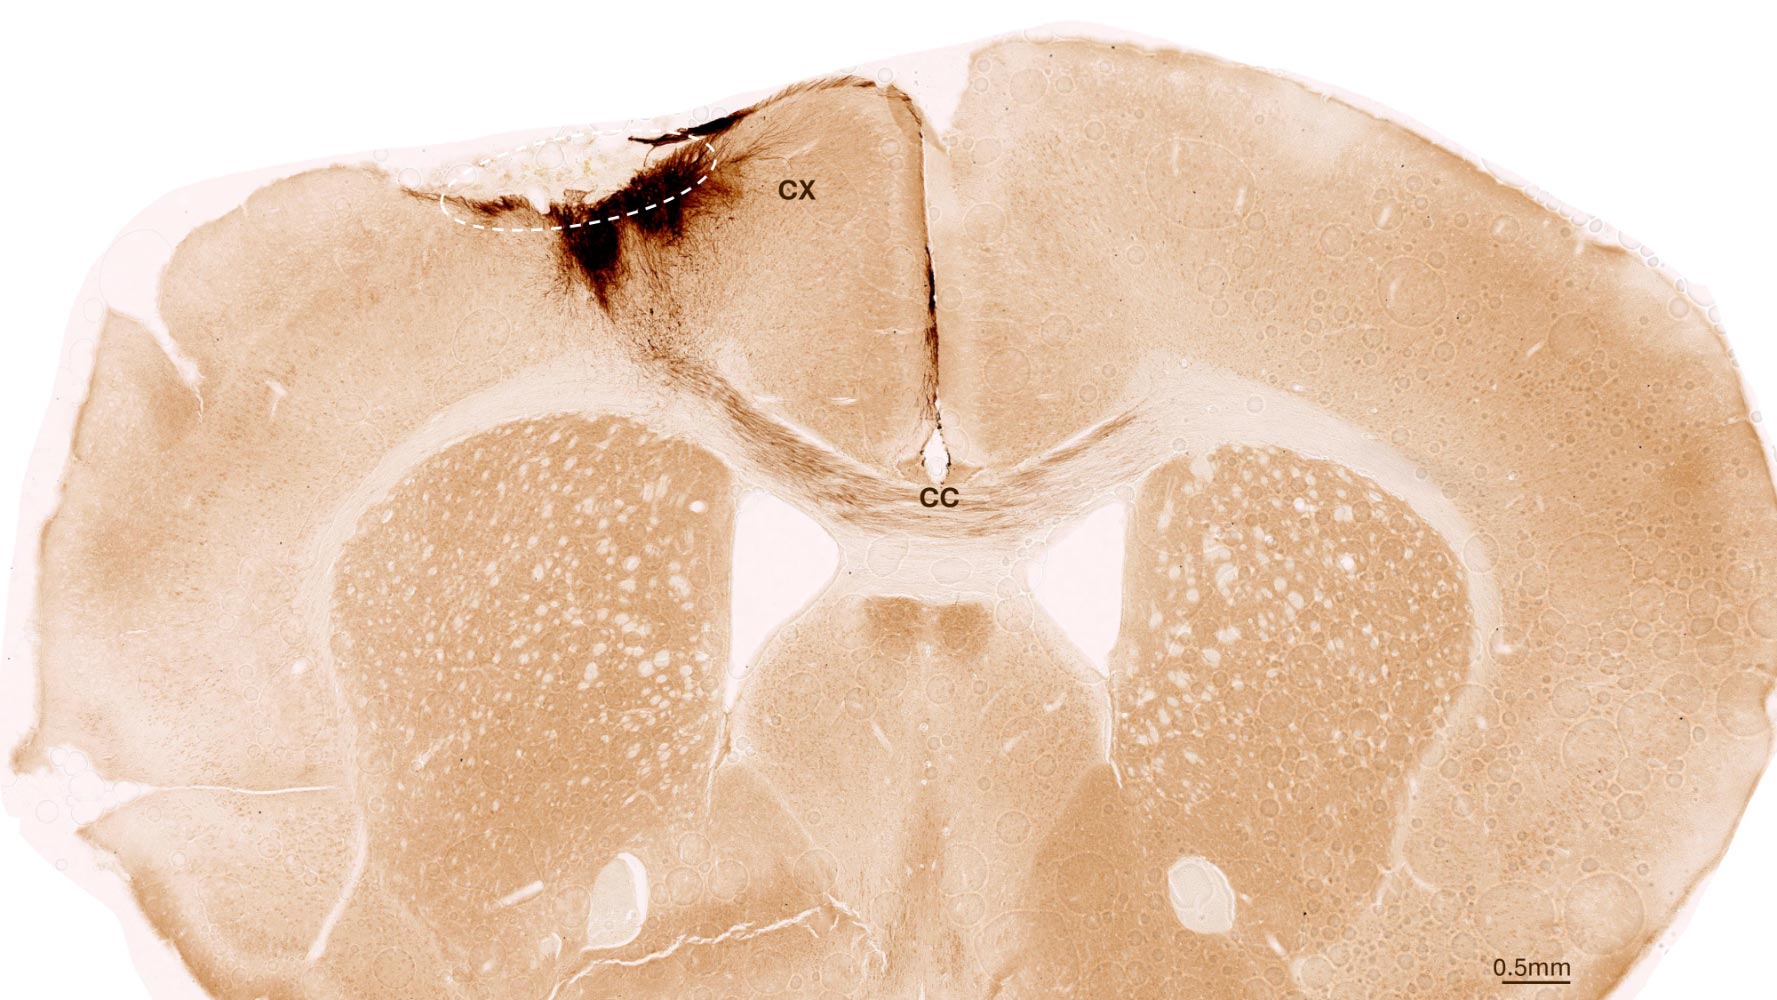

The research employed human neural stem cells, from which completely different cell varieties of the nervous system can type. The stem cells had been derived from induced pluripotent stem cells, which in flip could be manufactured from regular human somatic cells. For his or her investigation, the researchers induced a everlasting stroke in mice, the traits of which intently resemble the manifestation of stroke in people. The animals had been genetically modified in order that they might not reject the human stem cells.

One week after stroke induction, the analysis workforce transplanted neural stem cells into the injured mind area and noticed subsequent developments utilizing quite a lot of imaging and biochemical strategies. “We discovered that the stem cells survived for the total evaluation interval of 5 weeks and that almost all of them remodeled into neurons, which really even communicated with the already present mind cells,” Tackenberg says.

The researchers additionally discovered different markers of regeneration: new formation of blood vessels, an attenuation of inflammatory response processes, and improved blood-brain barrier integrity. “Our evaluation goes far past the scope of different research, which centered on the speedy results proper after transplantation,” Tackenberg explains. Fortuitously, stem cell transplantation in mice additionally reversed motor impairments brought on by stroke. Proof of that was delivered partly by an AI-assisted mouse gait evaluation.